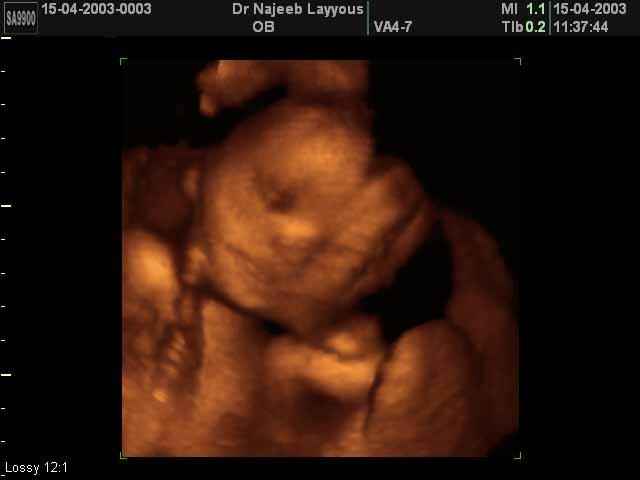

- Fetal Behavior Ultrasound Photos

Ultrasound Photos in 3D showing Fetal Behavior Inside the uterus | Dr N Layyous